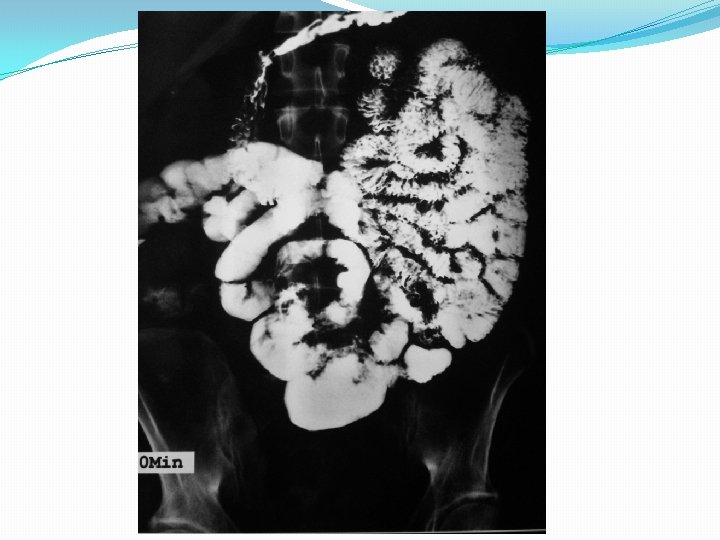

Barium studies of the gastrointestinal tract may suggest the diagnosis but are neither sensitive nor specific. They typically reveal thickening or nodularity in the antrum and a thickened or "sawtooth" mucosa in the small bowel.